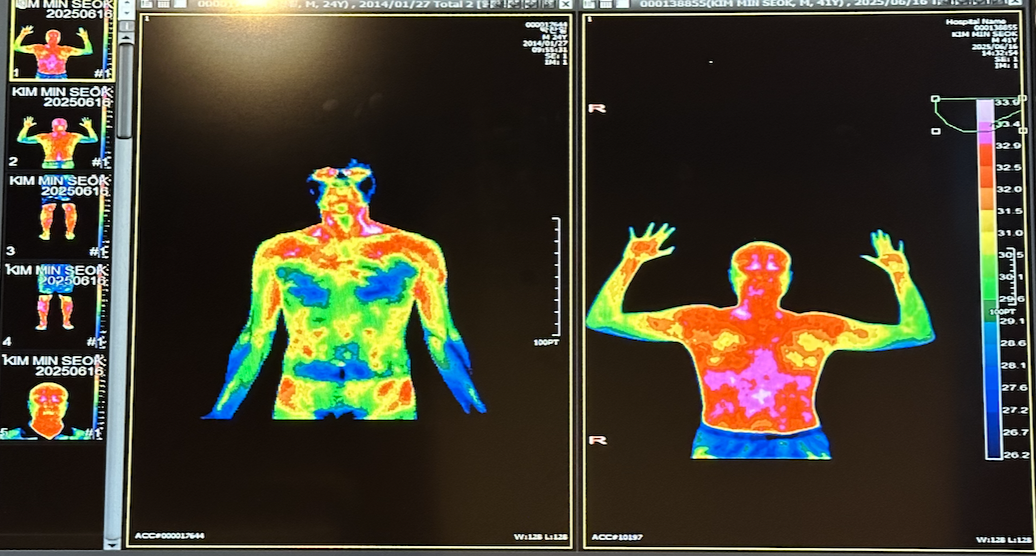

동일한 증상을 경험한 사람들이 있으면 신경과에 먼저 방문해 보길 강력하게 추천해주고 싶다. 입원을 하고 뇌파검사, 혈압검사, 열 사진, MRI 촬영 등의 검사를 받았는데, 진료하는 과정과 결과에 대한 해석이 생각보다 과학적이고 체계적이었다. 어떤 문제가 있는지 사진으로 직접 확인을 시켜주고, 그에 맞는 처방을 해줬기 때문에 신뢰를 가지고 치료에 임할 수 있었다.

스크린샷 2025-07-08 오전 9.29.27.png 결국 입원을 했다

스크린샷 2025-07-08 오전 9.30.58.png 왼쪽은 정상, 오른쪽이 나. 과부하 된 몸의 상태를 알 수 있었다